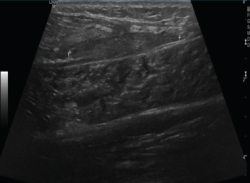

2.2. Roturas

Se observan áreas hipoecoicas de solución de continuidad de las fibras tendinosas(7), con retracción de los márgenes con la contracción muscular cuando la rotura tendinosa es completa (Figuras 9 y 10).

Figura 9. Corte sagital de una ecografía de rodilla: foco hipoecoico por rotura parcial del tendón cuadricipital.

Figura 10. Corte sagital de una ecografía de rodilla: ausencia del tendón rotuliano por rotura completa, con hematoma señalado en el trayecto del tendón.